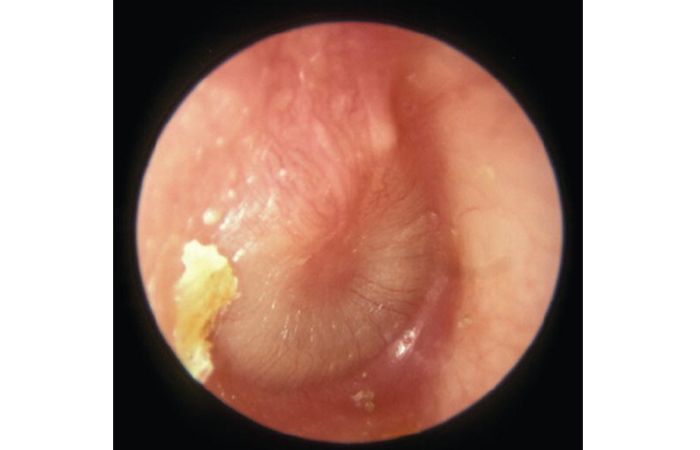

A normal eardrum (Figure 1) is translucent and greyish in colour. Acute otitis media causes inflammation of the eardrum (Figure 2).

Appearance of eardrum in acute otitis media: inflammation and loss of landmarks. A small amount of yellow earwax is bottom left

Source: Essential Paediatrics and Child Health, 4th ed, 2020. Rudolph M et al. Wiley. Reproduced with permission of Wiley.